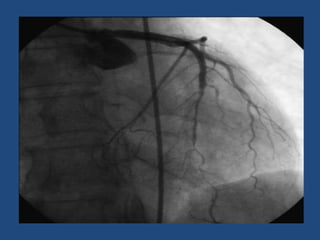

Incidencia Anatómica

• En el 75% afecta a la descendente anterior; en 20% a la

coronaria derecha, en 4% a la circunfleja y en menos del 1% al

tronco de la coronaria izquierda

• En la mujer, la disección compromete al árbol coronario

izquierdo en el 84% de los casos; en contraste, el 68% de los

hombres la coronaria derecha.